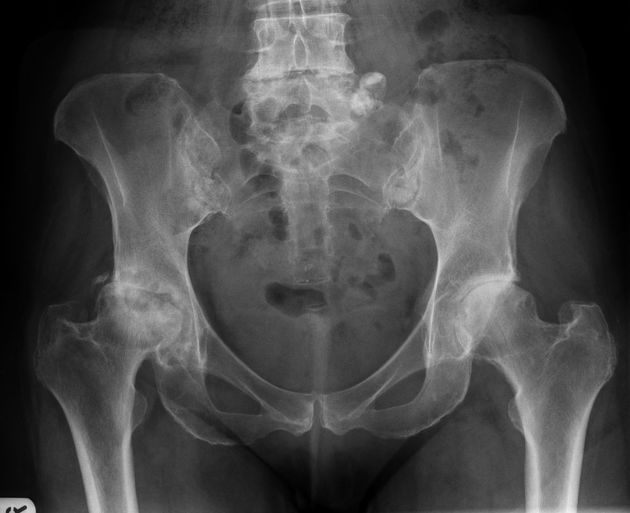

Take a look at the following example. Let us go through how we would systematically analyse this and the diagnosis.

Analysis and Diagnosis

D – This is a … X-Ray taken on ….., of the following patient….. Is there a previous X-ray to compare to

R – Commenting first on the quality, it is not rotated, there is adequate field of view, the projection is AP and lateral and it is adequately exposed as I can see the bones clearly

“On initial inspection, there appears to be a fracture of the neck of femur, but I will proceed to go through it systematically.”

B – Looking at the bones first, there is a subcapital fracture in the neck of femur. It is a closed, simple, transverse fracture. The fracture line extends through the junction of the head and neck of femur. There is no translation, rotation or shortening. There are no other fractures.

There are no obvious dislocations and the no abnormality in the texture of the bones

D – There are no degenerative changes in the joint spaces

E – There are no other man-made objects or signs of orthopaedic surgery.

In summary, this film shows an intracapsular fracture of the proximal femur.

Diagnosis

Neck of Femur Fracture

Image 1: Gaillard, F. Impacted subcapital fracture. Case study, Radiopaedia.org. https://doi.org/10.53347/rID-2717